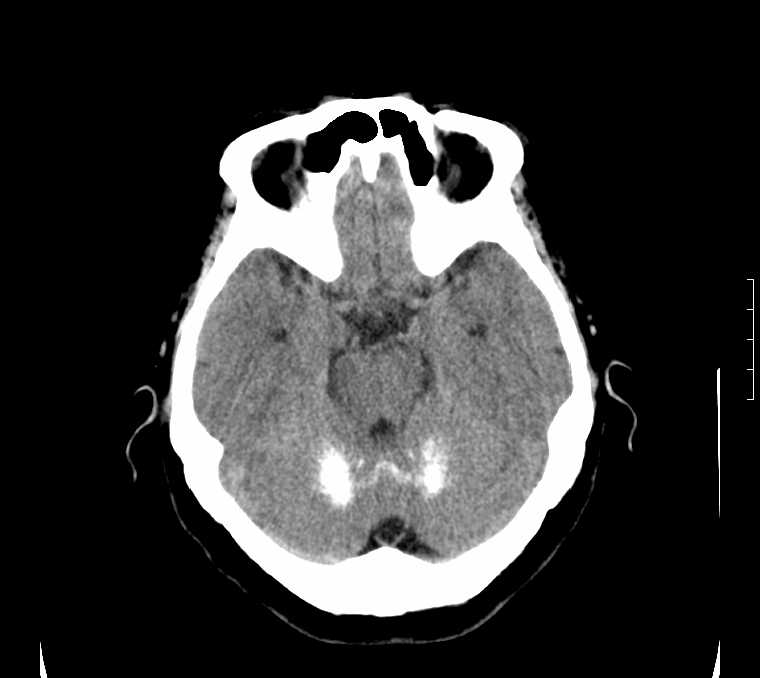

标题: CT24387:看看这例脑部改变!!

老年女性。头晕。

考虑:甲旁减。

fahr病

鉴别于特发性家族性脑血管亚铁钙沉着症(fahr`s病)与甲状旁腺机能低下之间,请结合临床及相关实验室检查。